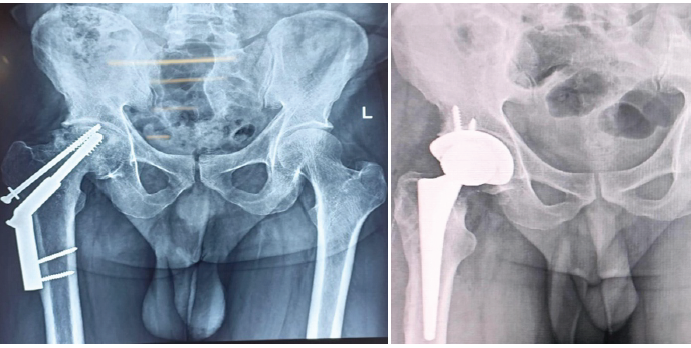

Primary THA has been proven to be effective in managing failed fracture fixation of the hip [1,6,9]. Failure modes such as osteonecrosis, screw cutout, and hardware loosening necessitate revision strategies that often involve extensive reconstruction [2]. Modern cemented and uncemented implants offer excellent long-term survival [3]. Proper pre-operative planning and radiographs are mandatory for adequate planning and implant selection. Augmentation materials such as Prolene mesh and cerclage wiring facilitate stability in deficient bone stock [8]. In our study, the usage of augmentation devices in appropriate cases proved higher functional outcomes and faster recovery in daily living. The usage of Prolene mesh (Fig. 2) for reconstruction of abductor deficiency has yielded excellent outcomes when compared to previous studies [8]. The addition of plates and screws (Fig. 3) has also yielded lower rates of failure and dislocation [2,5]. Ethibond sutures for soft-tissue reconstruction have been used in a few cases for severe soft-tissue damage due to previous surgeries and have not been described commonly in old literature. Younger patients with adequate bone stock benefit from uncemented THA(Fig 4,Fig 5), whereas cemented options are better suited for elderly or osteoporotic patients [5]. Adequate counseling is essential regarding potential risks, including dislocation, infection, and prolonged rehabilitation [4,10].

Figure 4: Case 4- Diagnosis: Chronic arthritis, right hip, post-dynamic hip screw. Procedure: Uncemented total hip arthroplasty.

Figure 5: Case 5 – Diagnosis: chronic arthritis right hip s/p – Fracture dislocation right hip with fracture right anterior and posterior column of acetabulum. Procedure: Uncemented total hip arthroplasty with Ethibond sutures.